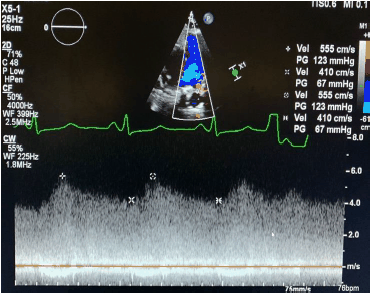

O sinal de fluxo registrado na imagem a seguir é compatível com